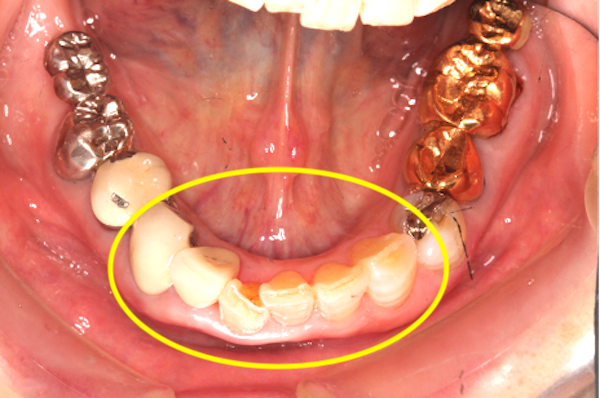

今回の患者様は、下の前歯がでこぼこしながら内側に入り、奥歯に比べて飛び出しています。本来、下の前歯は上の前歯の裏側に当たっているのですが、患者様の場合、下の前歯が上顎に突き刺さるような状態になっていました。

また、上の前歯は何度も治療を繰り返していました。さらに下の前歯の先端は削れていました。下の写真でお分かりでしょうか?

「エナメル質」という、歯の表面の白くて硬い外殻部分が失われ、「象牙質」という、歯の表面から2層目にあたる、少し黄色い部分が露出しています。

下の前歯が異常に削れてしまうというのは、噛み合わせがおかしいことの大事なサインです。